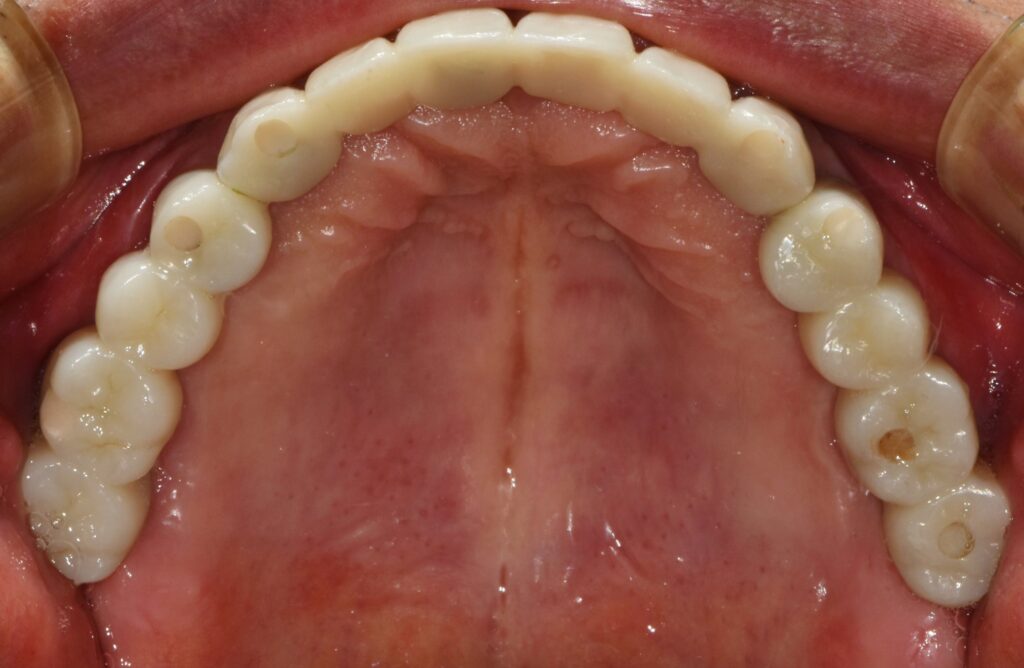

최종 보철물로 이행

임시 치아 기간을 대략 한 달에서 두 달 정도 갖고 모든 것이 다 좋다고 판단될 때 인상채득을 해서(본을 떠서) 최종 보철물로 이행을 해줍니다.

조화롭게 치료가 잘 된 모습입니다. 당연히 식사도 편하게 잘하시고 그 덕분에 생활에 활력이 넘치고 일이 잘 풀린다고 하셨습니다.